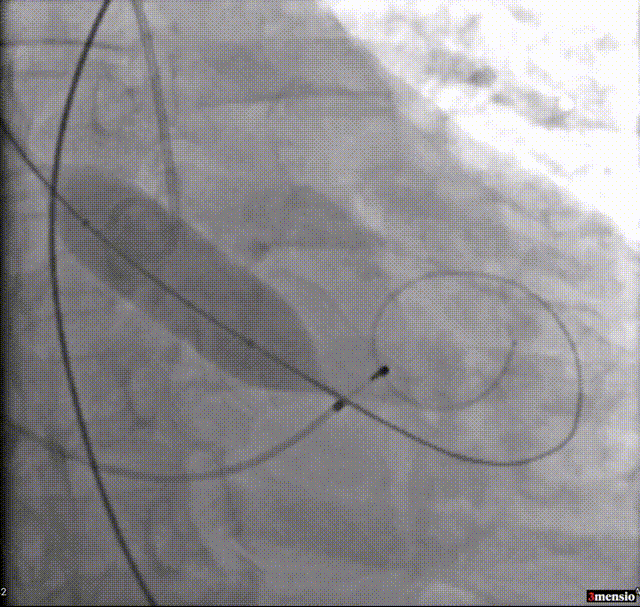

4.快速起搏下20mm球囊预扩;

球囊预扩